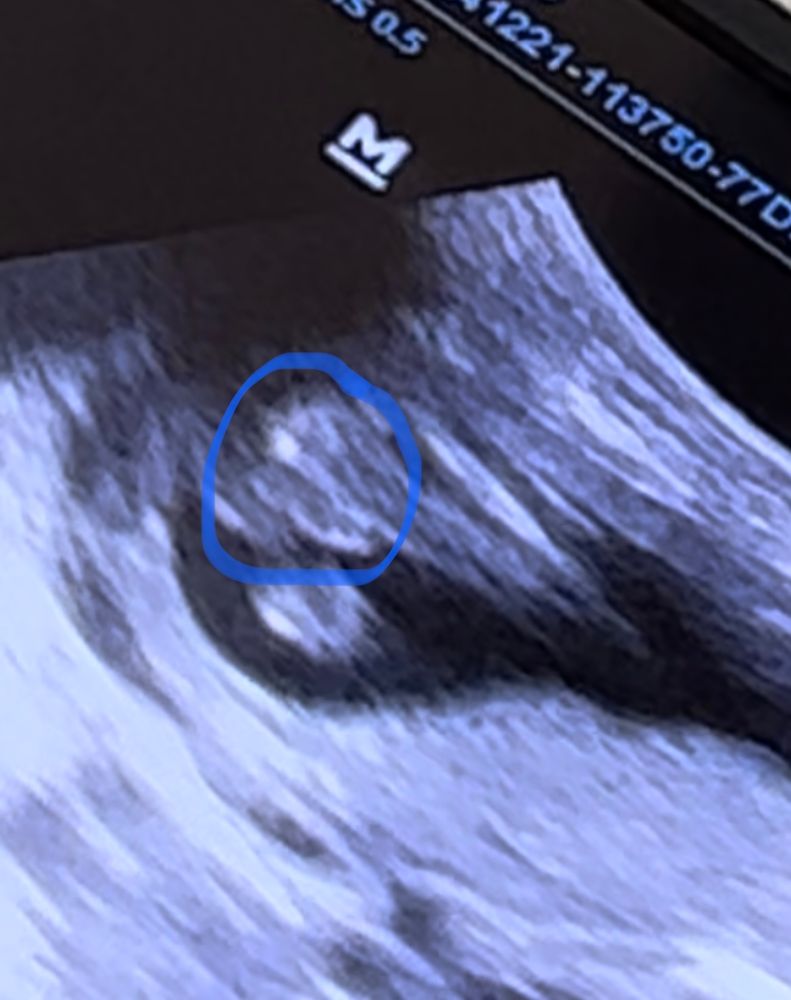

Изображение

👀👀👀

Мальчик вроде💙

Мне на мальчишку похоже

Кто понимает в узи, не терпится узнать кто у нас Пол